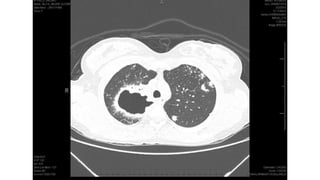

Miliary pattern

Intersticial Randomic micronodular distribution